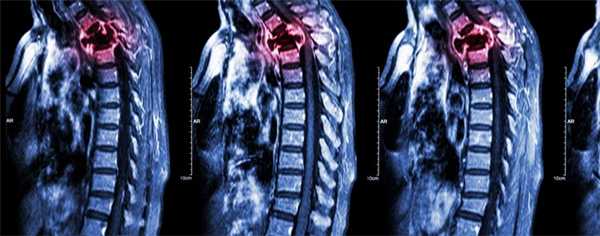

(Слева) Сагиттальный срез, Т1-ВИ с КУ, пациент с гистологически верифицированной мультиформной глиобластомой: на уровне С5-6 определяется интрадуральное экстрамедуллярное образование. Обратите внимание на отсутствие диффузного усиления сигнала мягких мозговых оболочек.

(Справа) На сагиттальном Т1-ВИ с КУ позвоночника, выполненном после резекции не накапливающей контраст мультиформной глиобластомы островка Рейля справа, на поверхности спинного мозга виден также не накапливающий контраст метастаз этой опухоли.